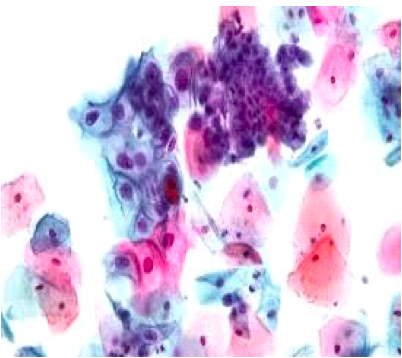

•     Papanikolau test

Od ostalih dijagnostičkih postupaka primjenjuju se: tumor markeri: SCC-skvamozni ćelijski karcinomski antigen, laboratorijska dijagnostika: KKS, sedimentacija, biohemijske analize i pregled urina-pružaju uvid u opšte stanje pacijentkinje, edukacija i savjetovalište